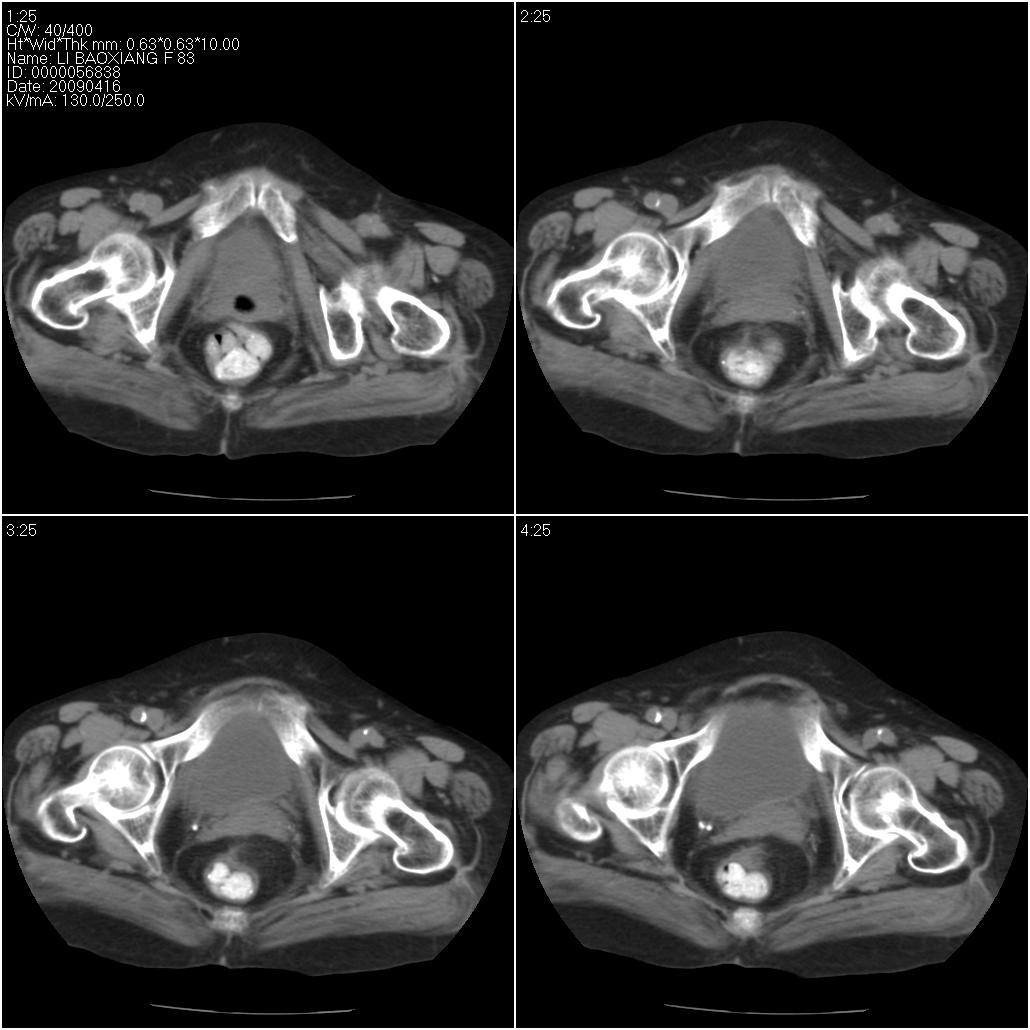

标题: CT19496:女性,83岁。阴道出血多年,患者一般情况良好。 [打印本页]

标题: CT19496:女性,83岁。阴道出血多年,患者一般情况良好。

乙状结肠病变累及子宫,建议结合妇科检查

考虑乙状结肠肿瘤累及子宫;建议行肠镜检查。

考虑:乙状结肠癌累及子宫,建议钡剂灌肠。

乙状结肠癌累及子宫

乙状结肠癌侵犯子宫可能性大。